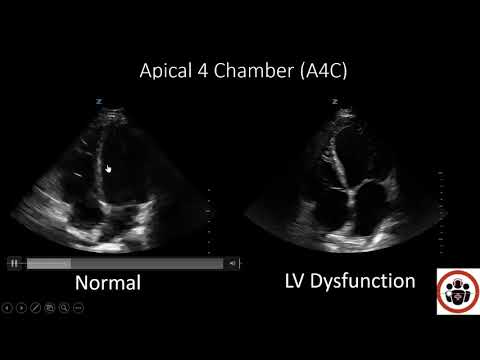

POCUS for LV systolic function

Episode 4: Assessment of LV Systolic Function

Assessing LV Function

Echocardiography Essentials: Assessing left ventricular global systolic function (LVF)

POCUS Cases 3: LV Systolic Dysfunction

Left ventricular systolic function (global assessment and visual estimation) for ICU